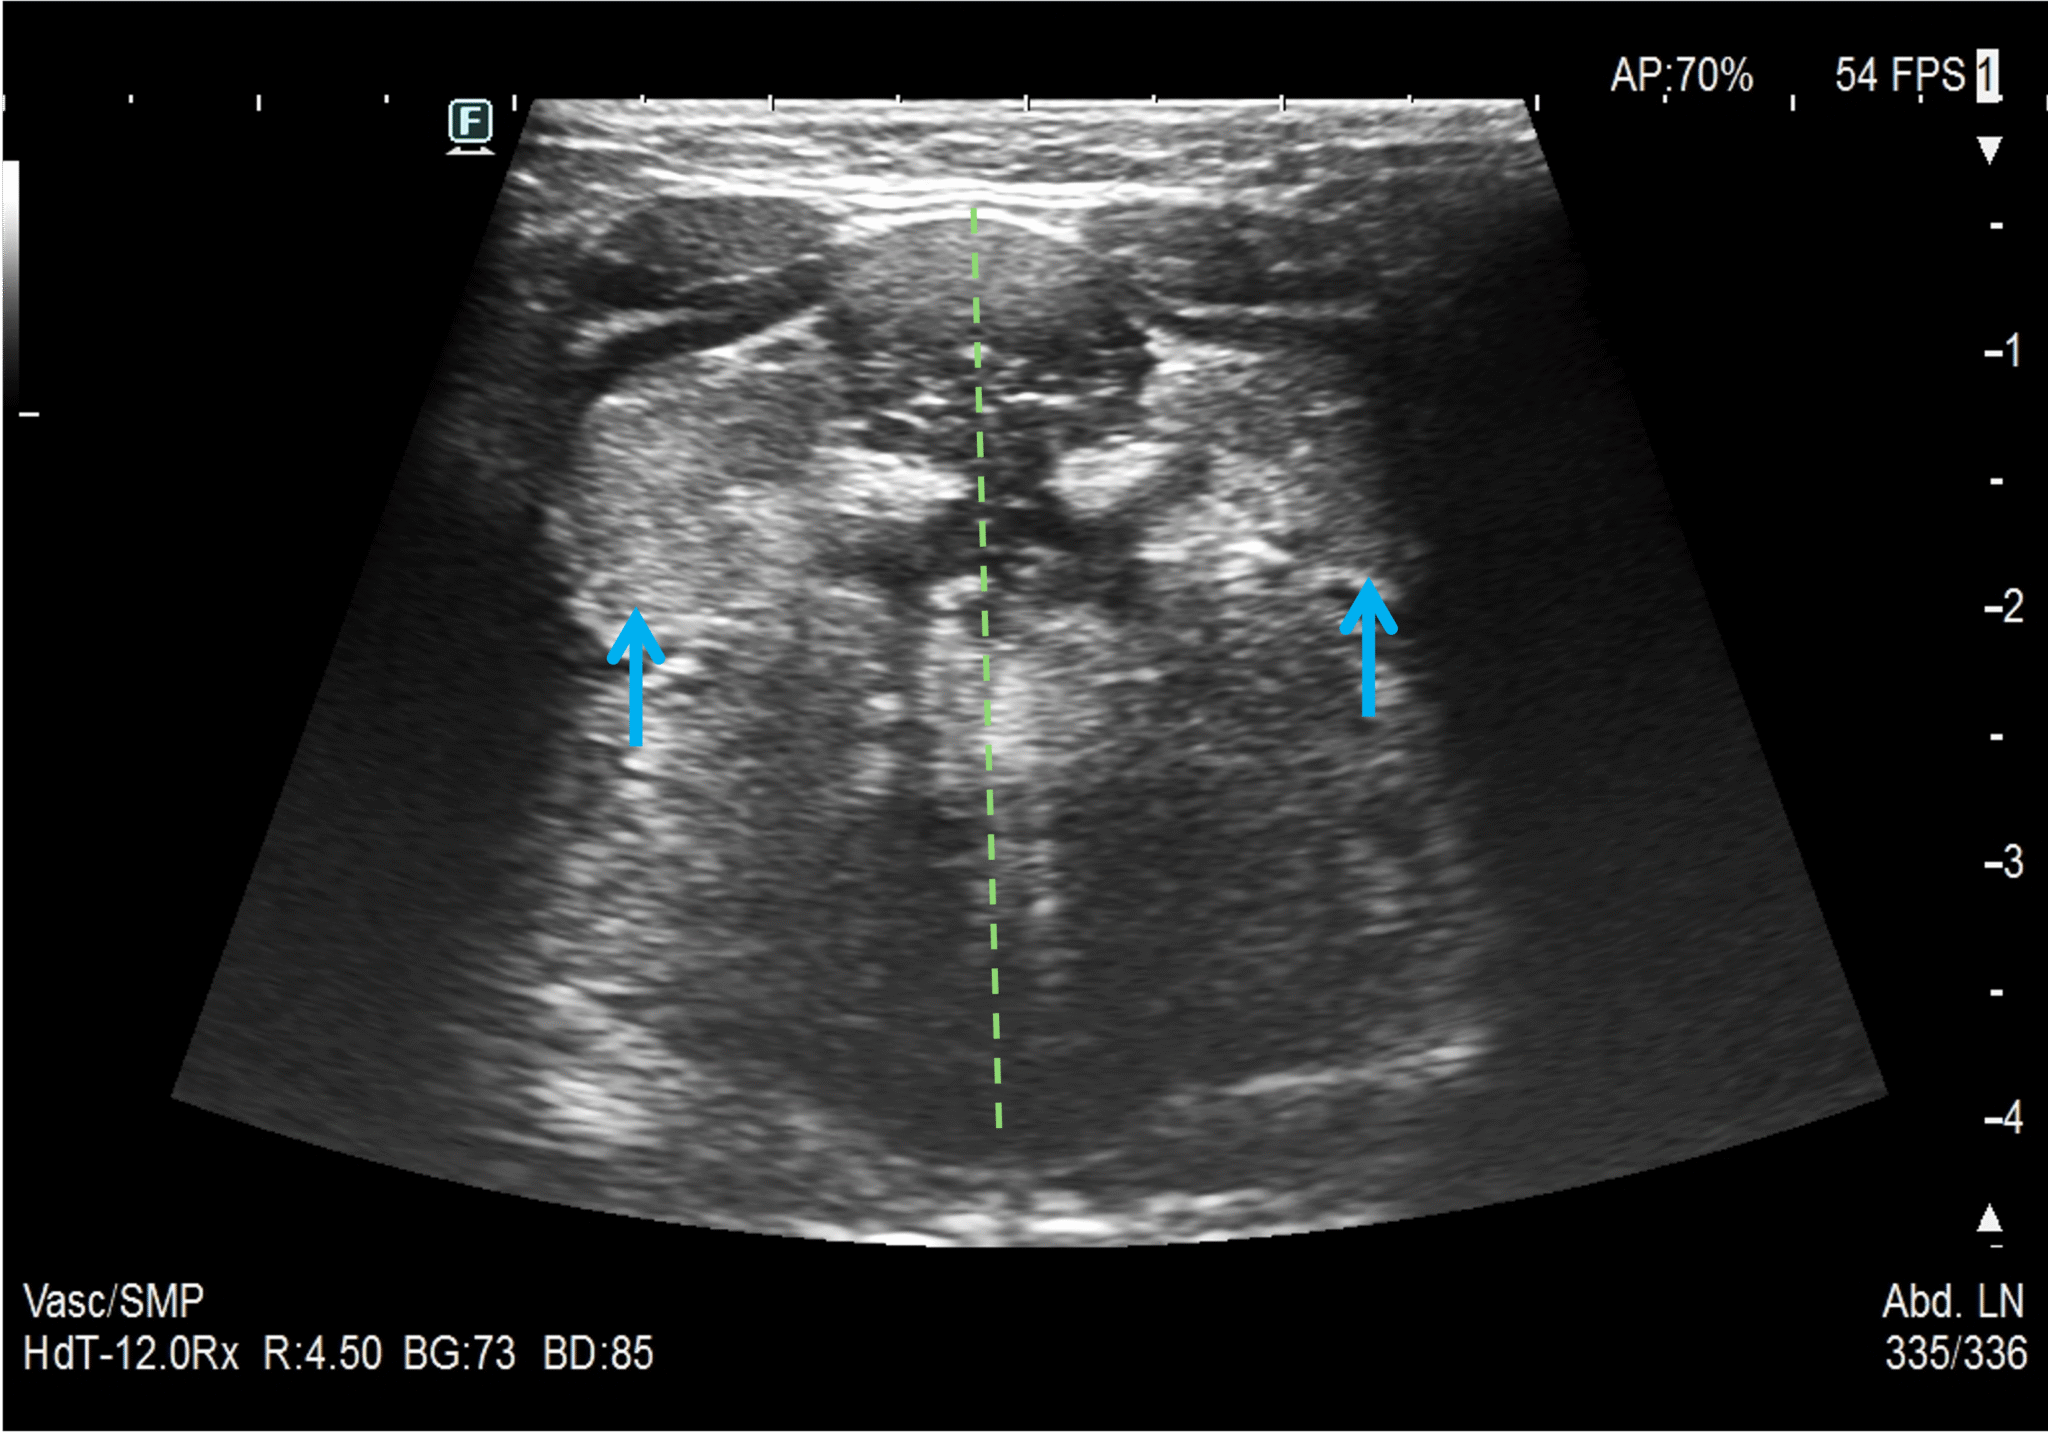

Ocena USG ślinianek obejmuje wszystkie główne gruczoły ślinowe – przyuszne, podżuchwowe i podjęzykowe oraz regionalne węzły chłonne. Najczęściej dziecko ułożone jest w pozycji leżącej na plecach. W zależności od badanego gruczołu prosimy o zwrócenie głowy w bok lub o ułożenie pośrodkowo i niewielkie uniesienie brody ku górze. W przypadku małych dzieci pomocne jest położenie dziecka na brzuchu rodzica lub opiekuna. Każda ze ślinianek powinna zostać oceniona w dwóch prostopadłych do siebie płaszczyznach.

Ślinianki podjęzykowe to małe gruczoły zlokalizowane w dnie jamy ustnej, w przedniej części przestrzeni podjęzykowej, do boku od mięśni bródkowych. Tylny biegun ślinianki podjęzykowej może się stykać z wyrostkiem górnym ślinianki podżuchwowej, a biegun przedni może łączyć się z biegunem przednim przeciwległej ślinianki. Celem uwidocznienia ślinianki w USG najczęściej poprosimy pacjenta o uniesienie brody ku górze, a głowice przyłożoną poprzecznie do okolicy podbródkowej kierujemy czołem ku górze. Taka pozycja pozwala na ocenę ślinianek w płaszczyźnie czołowej, przesuwając głowicę od brody w kierunku kości gnykowej. Jeśli to możliwe, po zrotowaniu głowicy o 90 stopni oceniamy ślinianki w płaszczyźnie strzałkowej. Echogeniczność i echostruktura ślinianek podjęzykowych jest zbliżona do analogicznych cech ślinianek podżuchwowych. Główny przewód wyprowadzający, czyli przewód podjęzykowy większy (przewód Bartholina) uchodzi najczęściej wspólnie z przewodem Whartona i jest niewidoczny w USG.

14. Ślinianki podjęzykowe w projekcji podbródkowej.